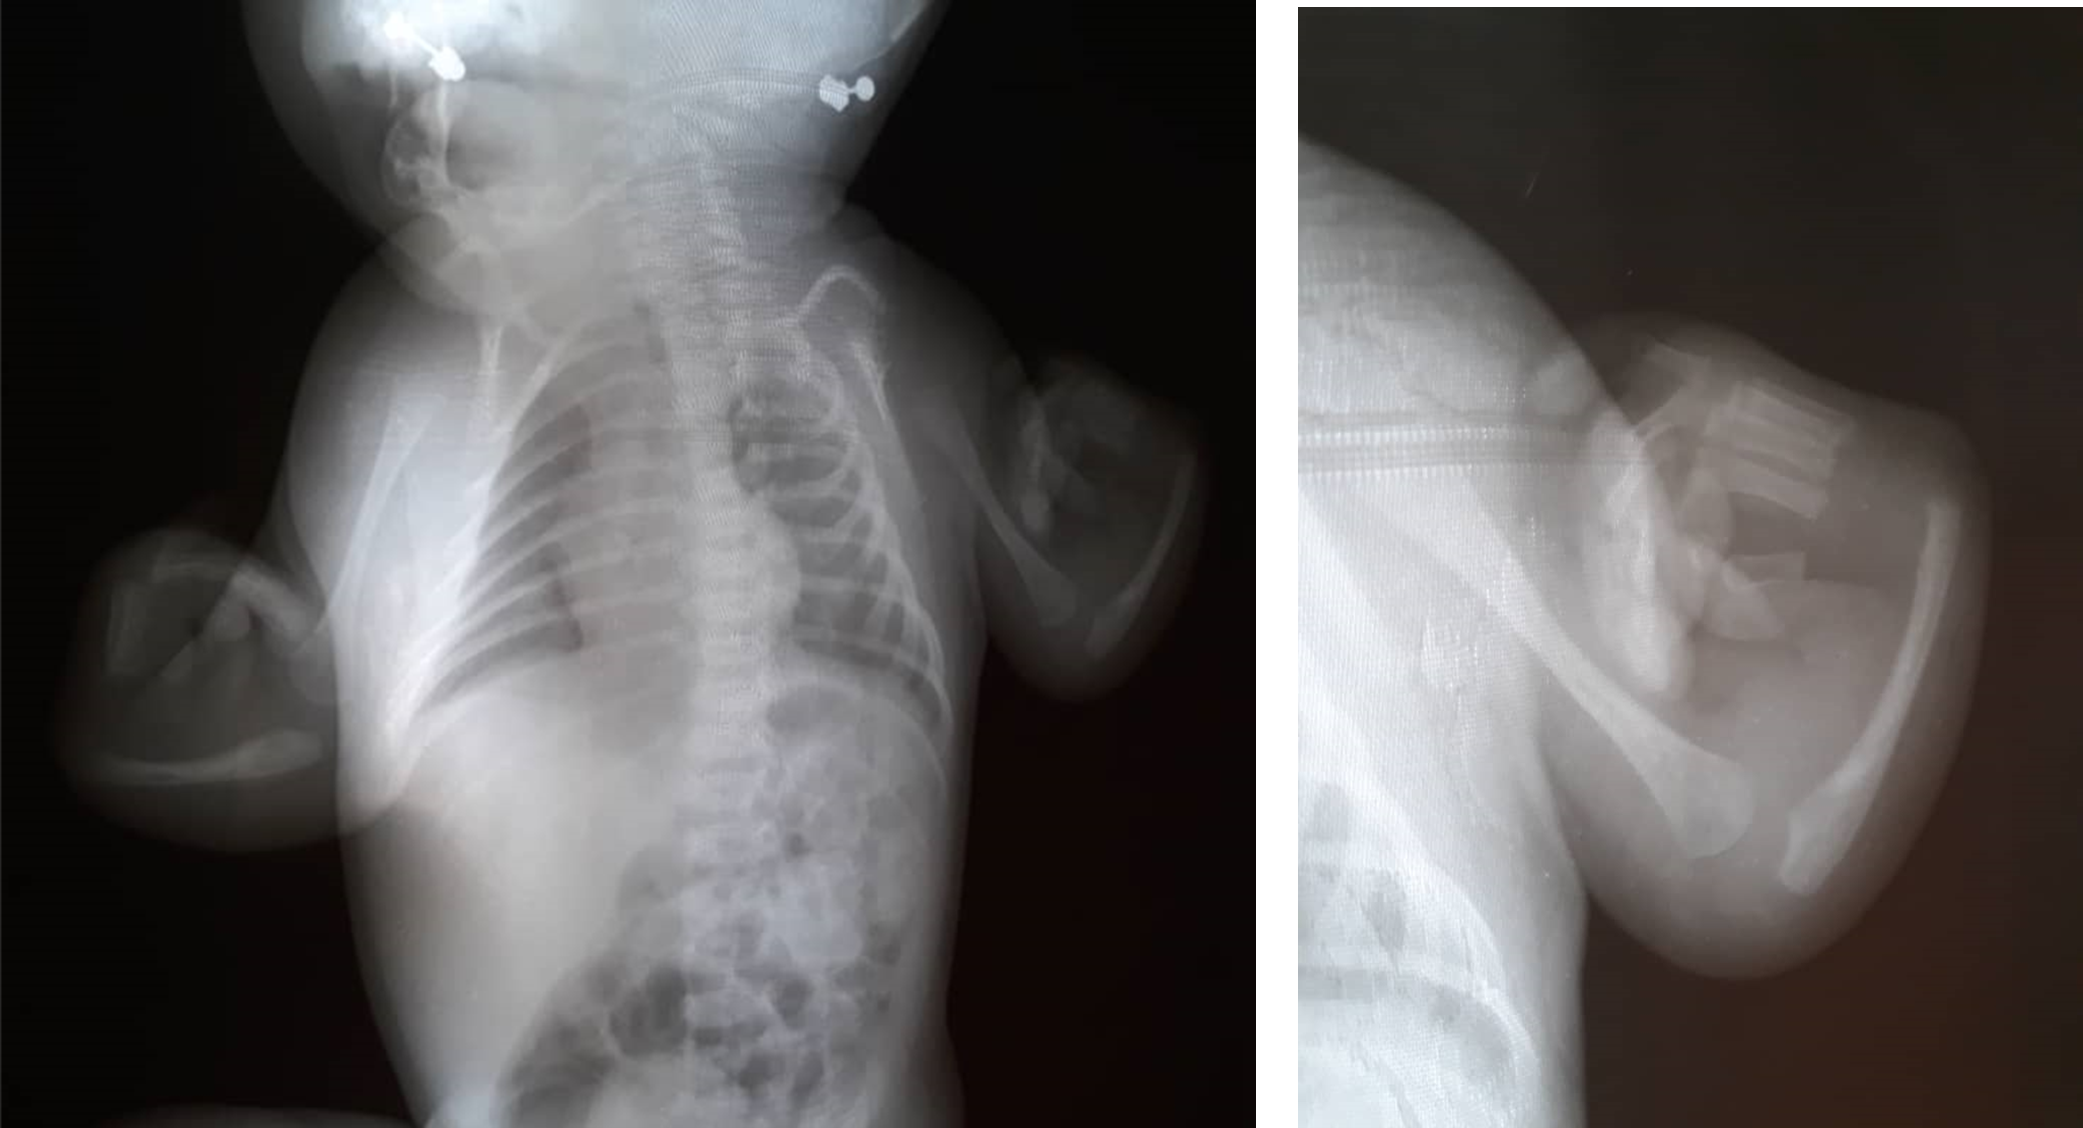

Diagnóstico prenatal de Trombocitopenia-Aplasia Radial (TAR): Reporte de un caso y revisión de la literatura

Ivan Aivasovsky, Lorena Rincones, Sergio Vergara, Andrés Parra, Andreina Zannin, Ameinada Ferrer, Ana Isabel Bracho, Isabel Fernandez, Luis Gustavo Celis

20-26